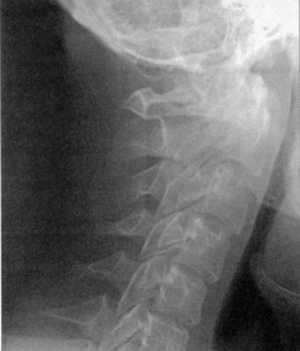

Диагностика. Рентгенография верхнего шейного отдела позвоночника в боковой

проекции выявляет расширение суставной щели Крювелье. В норме расстояние между

задней поверхностью передней дуги атланта и передней поверхностью зубовидного

отростка аксиса равняется: в положении сгибания -1,8 мм, разгибания - 2,2 мм,

в нейтральном положении - не более 2 мм (Hinck, Hopkins, 1960).

КТ и цифровая спондилография - важные методы диагностики вывихов атланта (рис.

1.7 и 1.8). МРТ позволяет определить не только дислокацию атланта, но и степень

компрессии спинного мозга (рис. 1.9).

Рис 1.7. Ротационный вывих атланта по

данным цифровой спондилографии |